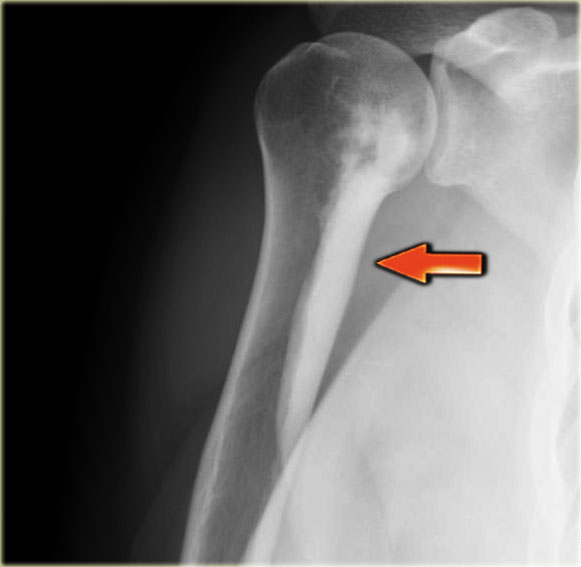

Melorrheostosis of proximal humerus.